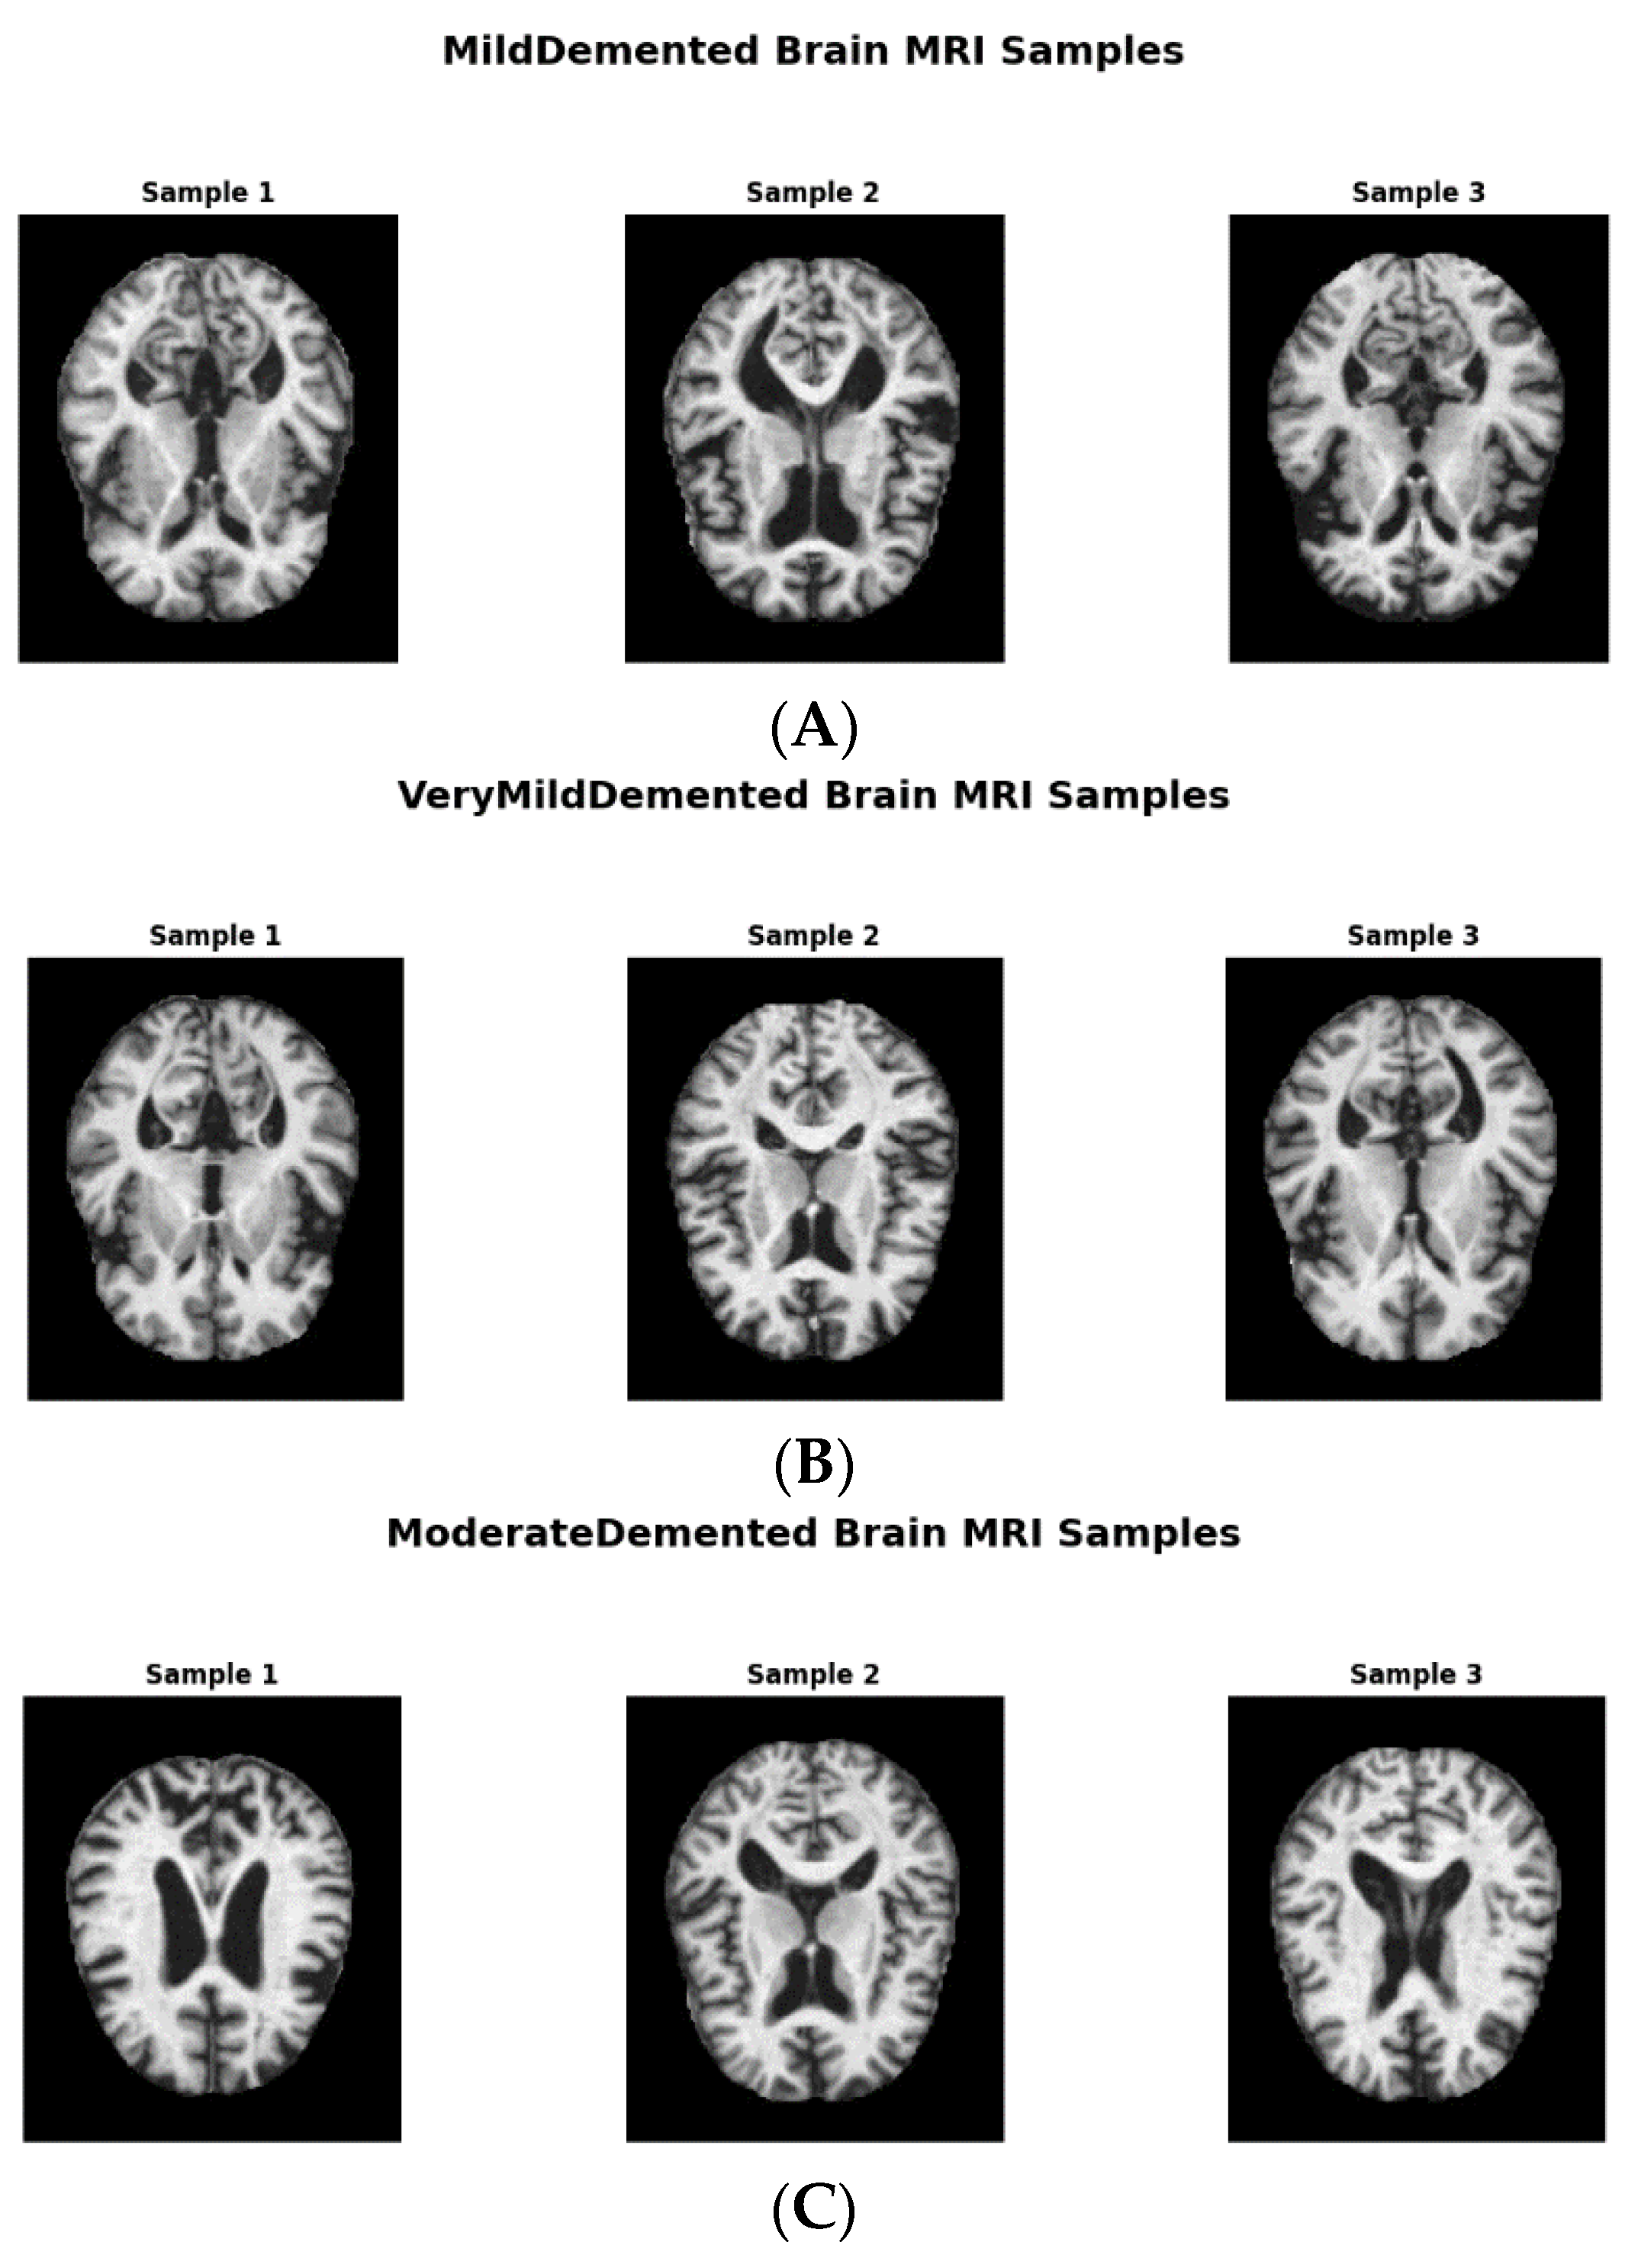

We obtained the initial AD dataset from the Kaggle website, available online: https:// www.kaggle.com/datasets/tourist55/alzheimers-dataset-4-class-of-images (accessed on 14 April 2024) [25]. It provides high-quality MRI scans organized into four classes representing distinct AD stages: VeryMildDemented, MildDemented, ModerateDemented, and NonDemented. Such structured categorization allowed us to take a multi-stage classification approach, as is required for early AD detection and progression monitoring [25]. Figure 1 shows image samples from each class, while Figure 2 shows augmented data samples and our implementation process to address class imbalances and issues with data homogeneity.

Figure 1. (A) MildDemented brain MRI samples. (B) VeryMildDemented brain MRI samples. (C) ModerateDemented brain MRI samples. (D) NonDemented brain MRI samples.